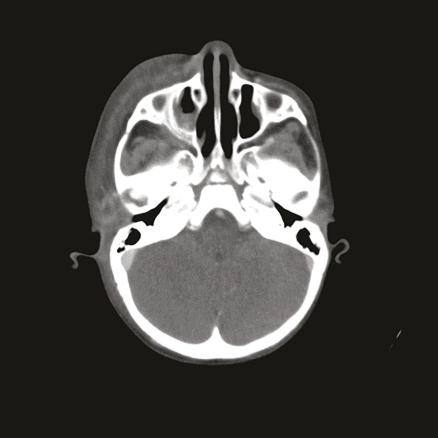

Une patiente âgée de 3 ans est suivie pour un lymphome de Burkitt à double localisation maxillaire et abdominale avec envahissement médullaire, mis sous protocole de chimiothérapie GFAOP/LMB 2005. Trois mois après le diagnostic et quinze jours après une cure de chimiothérapie, elle présente une écorchure post-traumatique au niveau de la joue droite, négligée par la famille. Devant l’apparition de fièvre et l’extension de la lésion (fig. 1 ), la famille consulte. L’examen, à l’admission, trouve une patiente fébrile, en choc septique, avec un tableau de fasciite nécrosante : tuméfaction jugale droite de 7 cm, très douloureuse à la palpation, chaude, dure et centrée par un placard de nécrose de 5 cm de diamètre, associée à un œdème palpébral homolatéral. La tomodensitométrie (TDM) objective une cellulite préseptale droite avec infiltration phlegmoneuse des parties molles (fig. 2 ). Une antibiothérapie à large spectre est administrée. Après correction du bilan d’hémostase, une nécrosectomie avec résection profonde des muscles de l’hémiface droite est réalisée, suivie dans un deuxième temps d’une greffe cutanée. L’évolution clinique est favorable. Après quatre ans de suivi, les résultats actuels montrent une amélioration significative (fig. 3 ).